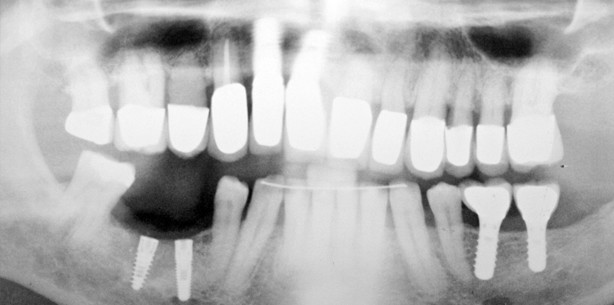

Ein Patient (männlich, 60 Jahre alt) hat sich zwecks Versorgung der vor drei ­Monaten inserierten Implantate Regio 45–46 vorgestellt (Abb. 1). Anhand der vorgelegten Behandlungs­unterlagen wurde festgestellt, dass keine Implantationsschablone angefertigt bzw. intraoperativ verwendet wurde. Aufgrund der extremen Neigung des ­Implantats 45 (die das Einsetzen von zwei Abdruckpfosten nebeneinander nicht erlaubte) war eine Abformung (weder geschlossen noch offen) undurchführbar. Diese Problematik ist in Abbildung 2 zu erkennen, wo die Kollision von ­Abdruckpfosten grafisch dargestellt wurde. Zur Lösung des Problems wurde folgendermaßen vorgegangen: